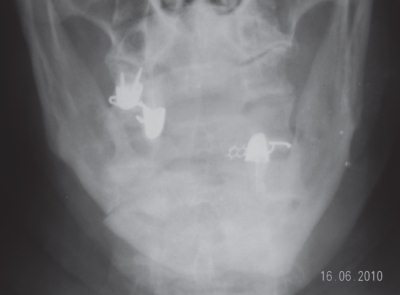

Также применялось рентгенологическое обследование нижней челюсти в прямой и боковой проекциях (рис. 1).

Рис. 1. Больная И., 68 лет. Рентгенограмма нижней челюсти у больного с переломом нижней челюсти: а – прямая проекция, б – боковая проекция